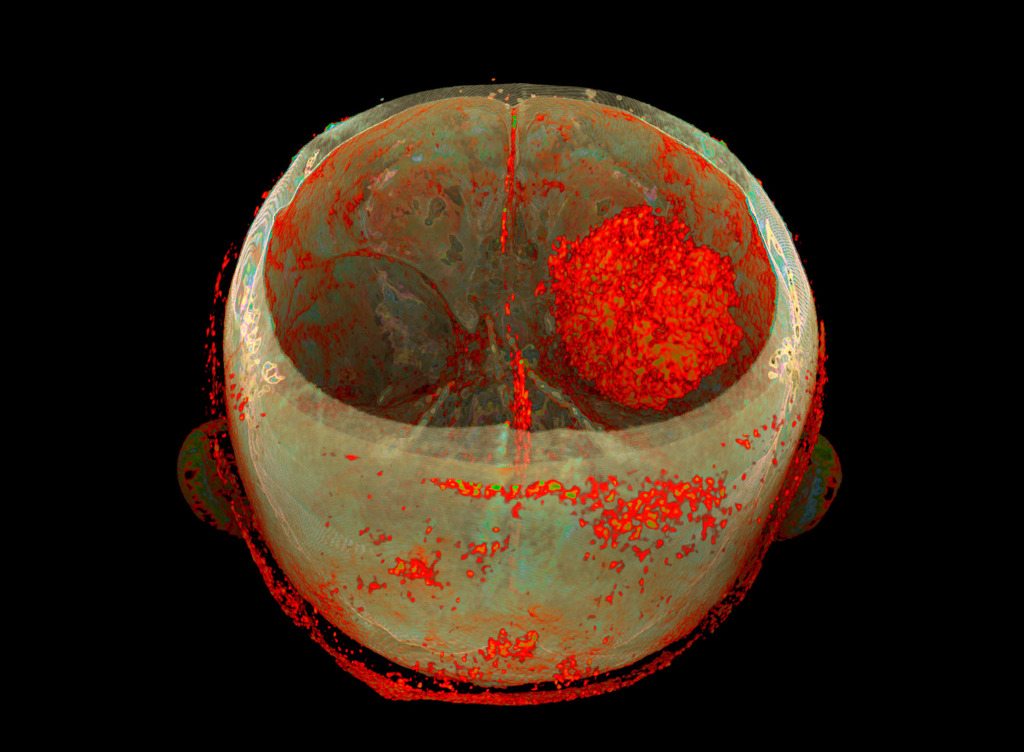

The program for processing radiological images (DICOM archives) allows you to create and look at a three-dimensional image from different angles.

If you change the location of the virtual lens, thereby changing the perspective, you can get such images.

I simply create a table where the radiological density of the material can correspond to any colour.

After combining different shades, I only have to choose what I like the most.

No. Tissues with different densities are best suited to visualisation by CT imaging.

Lungs and heart, bones and muscles or organs injected with a contrast agent reveal the best structure and anatomy.